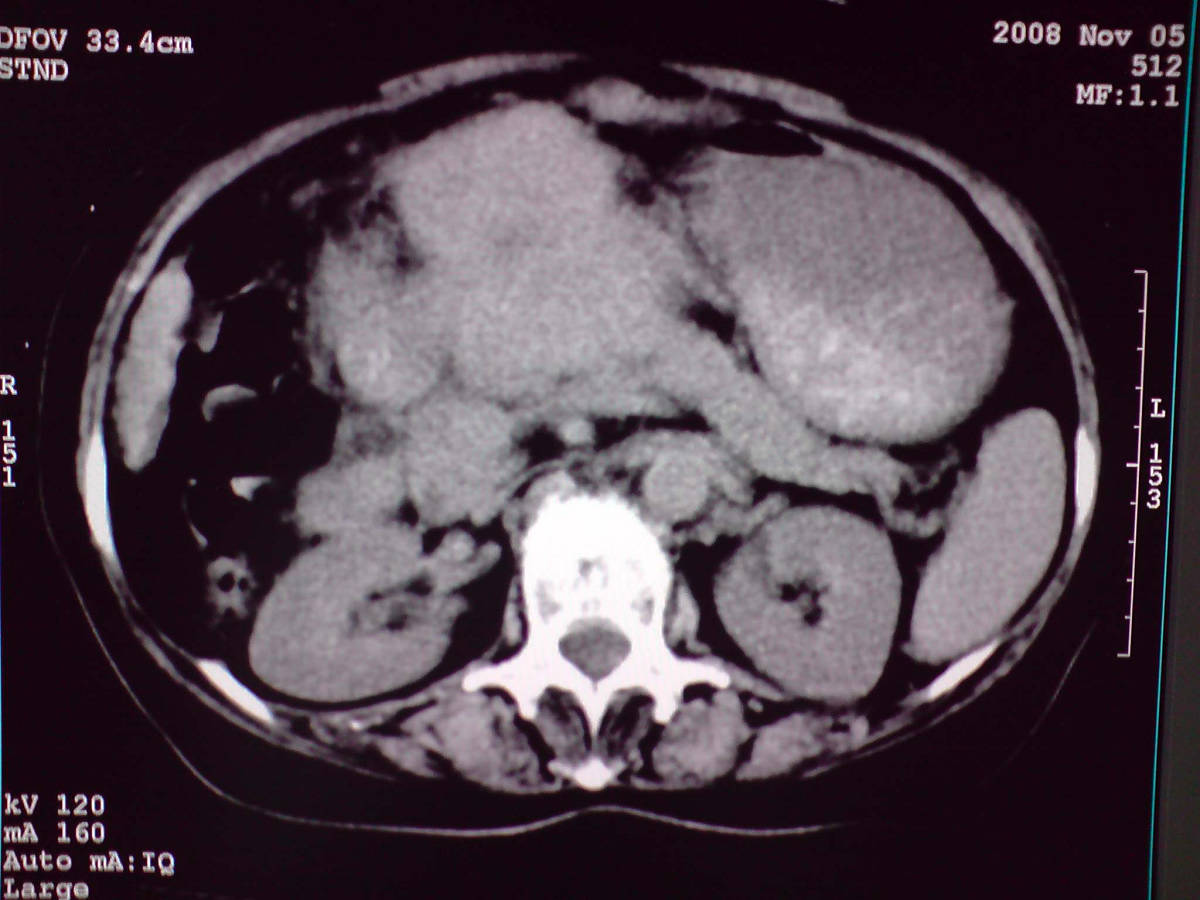

女性,60岁,上腹不适、自感胃部疼痛

小网膜区见类圆形软组织密度肿块,密度不均,内见不规则低密度区,与肝左叶分界模糊,肝脏体积缩小,密度不均匀,边缘呈波浪状,尾状叶明显增大,脾脏下缘明显超出肝脏下缘。

意见:肝硬化并外生性肝癌,建议增强扫描。

肝脏比例失调,形态失常,外缘呈波浪状,腹腔内肿块内见低密度区并与肝脏界限欠清

考虑外生性肝癌,左肺下叶占位,肝硬化

有肝硬化背景,肝胃间隙见不规则形,且密度不均匀的占位性病变,与肝左叶分界不清,首先考虑外生性肝癌可能性大,不排外肝胃间隙恶性占位肝脏受侵可能性。左肺下叶结节影,其内见空泡征,边缘见毛刺,从一元化的角度首先考虑转移。

1 肝脏各叶比例失调,形态失常,外缘呈波浪状。右叶萎缩,左叶 尾叶增大。2 腹腔内软组织密度肿块,低于肝实质密度,内见低密度区,并与肝脏界限欠清。腹膜后见肿大淋巴结,并与腹腔肿块关系密切。3 左肺下叶肿块,见边缘毛刺征及胸膜凹陷征,并与近肺门侧见异常血管相连。

综合考虑:左下肺周围性肺癌伴腹腔 腹膜后淋巴结转移!另:肝硬化!

感谢大家的讨论,今天拿到病理结果是肝细胞癌